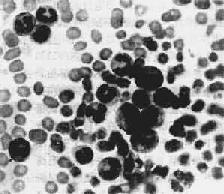

1.周围血像周围血白细胞显著增多,数量正常或减少者少见。CML时白细胞增多尤为明显,多在10万~至80万/μ1之间,少数甚至可超过100万,其中大多数为较成熟的中、晚幼和杆状核粒细胞,早幼粒和原粒细胞很少(图11-7)。嗜碱性和嗜酸性粒细胞也增多。CML时中性粒细胞内碱性磷酸酶常缺如或降低。这点有助于与类白血病反应相区别。CLL血白细胞总数多在3万~10万/μ1之间。血像单一,绝大多数为成熟的小淋巴细胞,只有少数幼淋巴细胞。慢性白血病早期贫血较轻,血小板无明显减少。CML时血小板常增多。晚期有明显贫血和血小板减少。

图11-7 慢性粒细胞性白血病

周围血内白血病细胞主要为中幼粒细胞